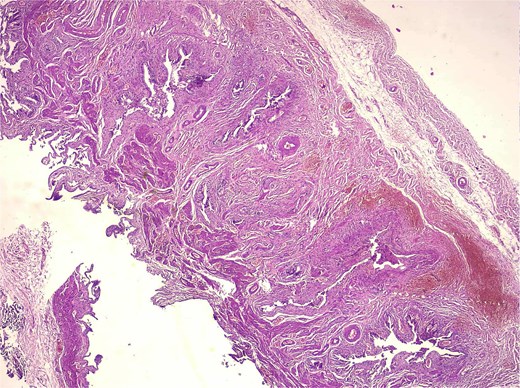

Histological analysis showed mucosal invaginations forming Rokitansky–Aschoff sinus–like diverticula surrounded by hypertrophic smooth muscle bundles, consistent with adenomyosis. The stroma exhibited lymphoplasmacytic infiltrates, hypertrophied nerve fibers, and vascular dystrophy. In deeper sections, areas of vascularized granulation tissue contained trabecular bone formation, confirming osseous metaplasia. No dysplasia or neoplastic proliferation was identified (Figs 2–4).

Medium-magnification histology (adenomyosis + osseous metaplasia zone, H&E) medium-power view showing complex architecture of deep mucosal glands and diverticula embedded within thickened smooth muscle bundles. Chronic lymphoplasmacytic inflammation is present, and trabecular bone consistent with osseous metaplasia is detected in deeper sections.